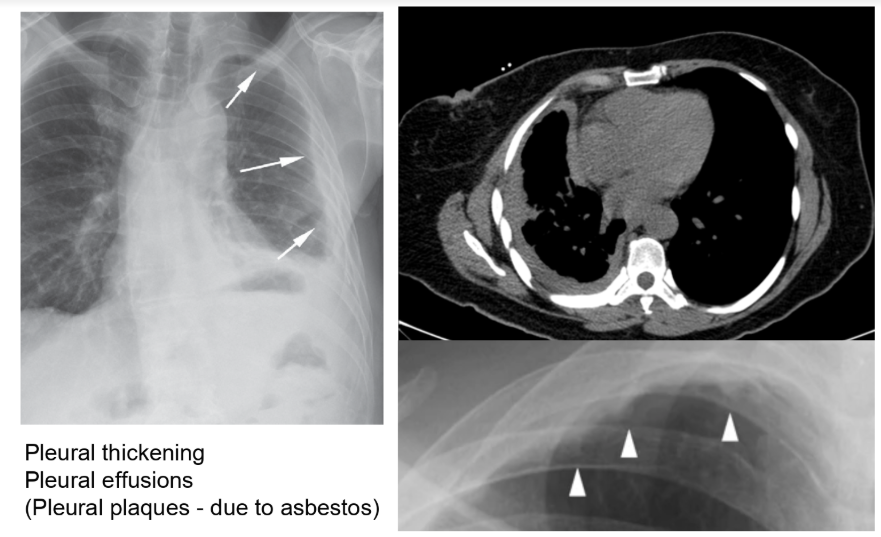

Imaging

CXR

CT chest

-> pleural plaques, pleural thickening, pleural effusions